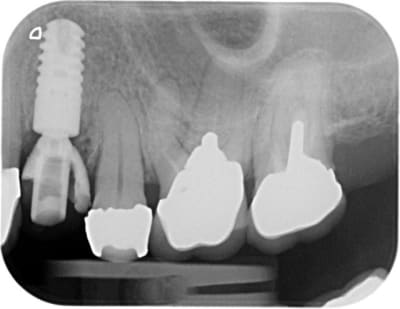

-ext 24 car mobilité type 2 + implant immédiat + couronne prov. en sous occ.

En ce qui concerne le choix entre ccc et ccm, il faut savoir que 90 % de mes couronnes sont en emax, mais dans le cas de racines extrêmement colorées ( ce qui est le cas ici)mon choix se porte sur des ccm classiques pour masquer ces colorations radiculaires que même une chape opaque sur emax ne peux dissimuler aussi bien qu'une ccm.

Mais ici il s'agit de dents ant sur racines naturelles, et toi tu montres une emax trans-vissé sur implant sur une dent post.

Cela n'a rien a voir. On ne peut pas comparer ce qui n'est pas comparable.

- la limite sur une couronne implantaire est souvent plus enfoui par choix ou par obligation qu'une couronne

- le biotype est souvent plus épais en post qu'en ant.

- la finition de la chape métal vest peut être plus proche de la ligne de finition vest du fait de sa finesse/chape pressé emax.

- tu cimentes tes ccm: ciment blanc opaque.

- tu colles tes emax. composite non opaque.

Pour avoir fait l’expérience plusieurs fois je préfère dans ce cas précis et pour ces raisons des ccm que des emax.

l’esthétique sera beaucoup facile a gérer surtout avec un cas plurale et symétrique.